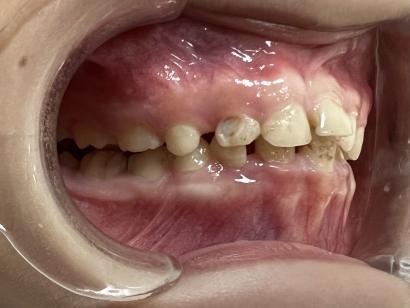

案例二:

治疗前